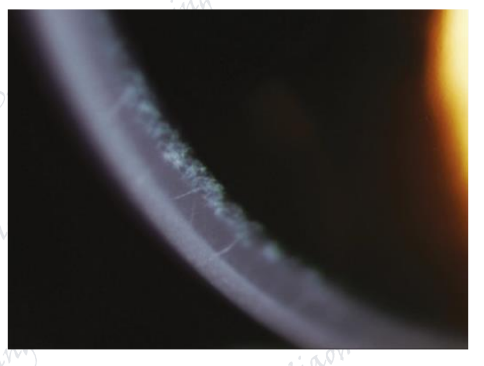

角膜色素环即Kayser-Fleischer环,简称K—F环,是Wilson病的一个常见特征表现,约95%的Wilson患者可见。Wilson病为常染色体隐性遗传病,表现为全身多个组织的铜沉积,周边角膜DM呈黄-棕色或绿色环。

图片

图19.DM色素性沉积物